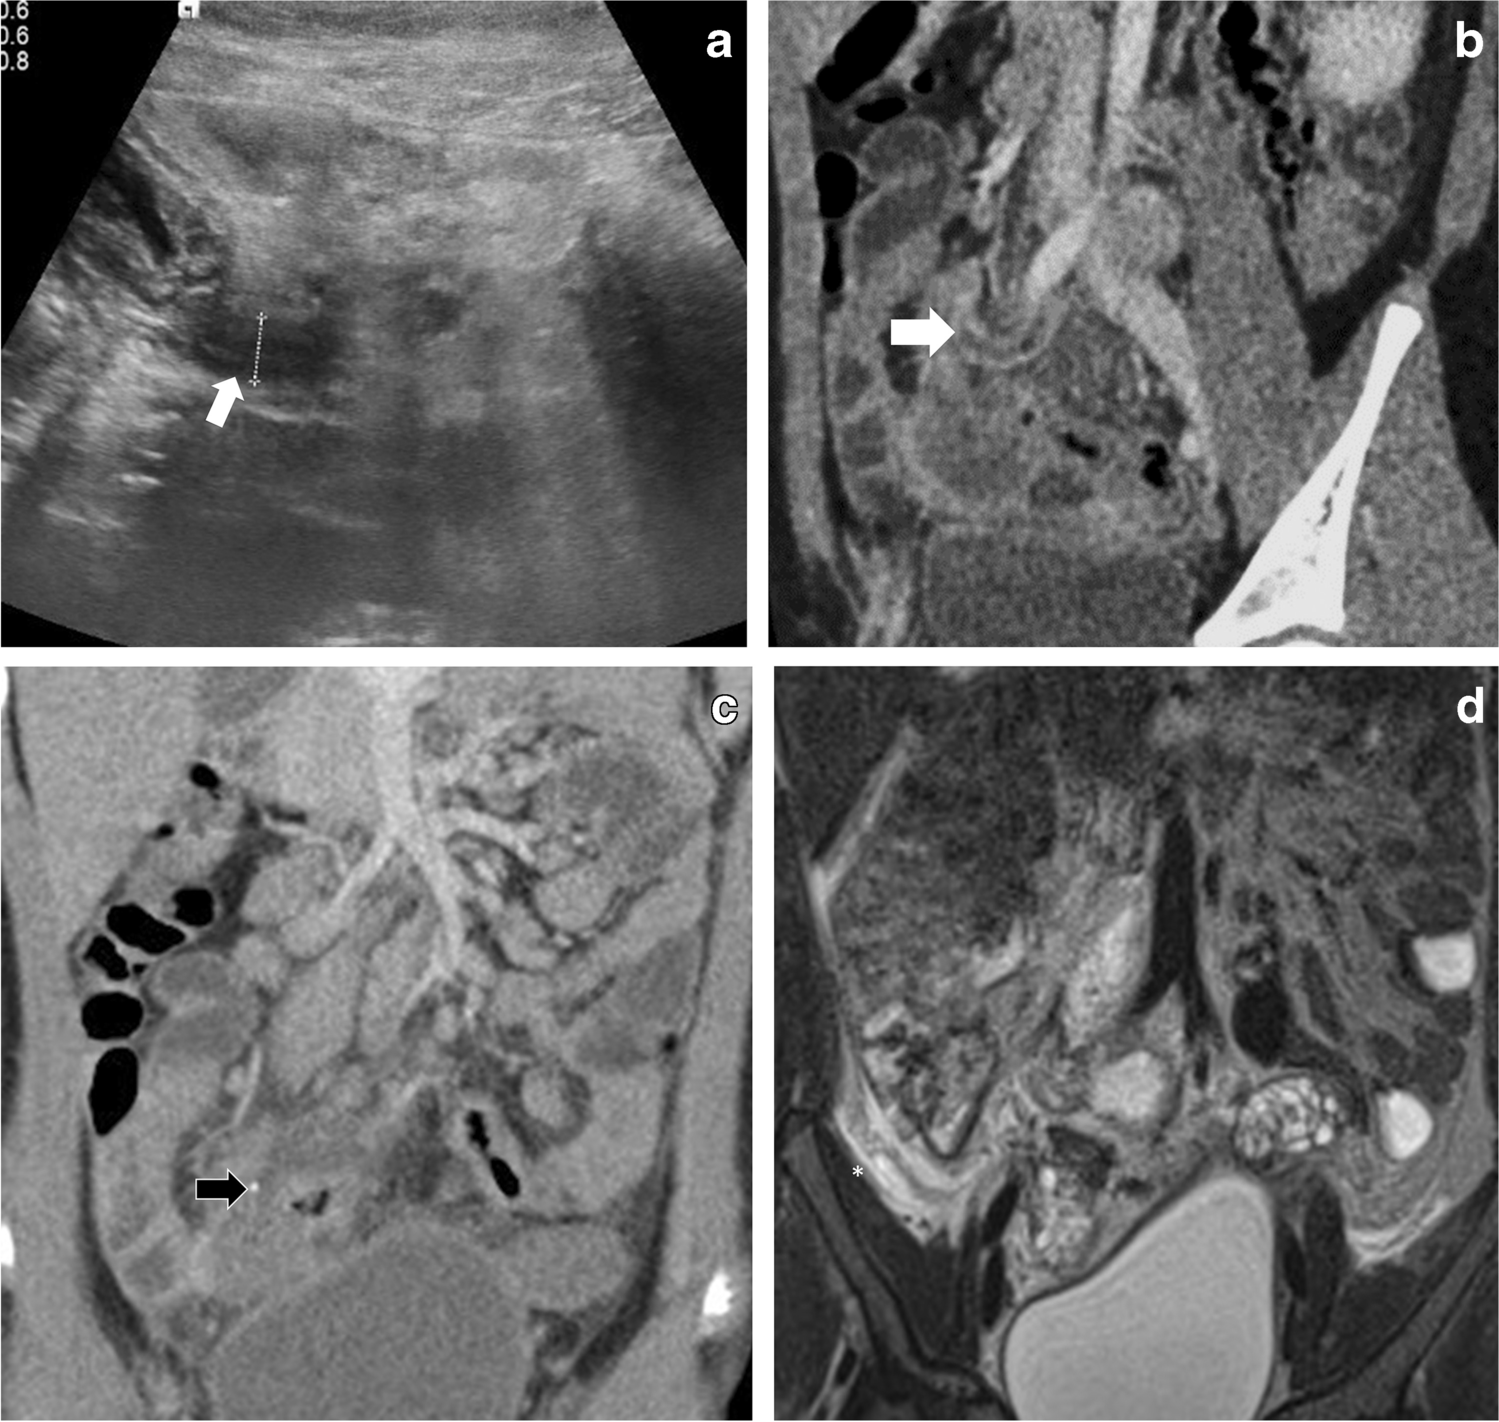

Fig. 4

Case 23: a 7-year-old boy with abdominal pain, vomiting and fever. a, b US abdomen transverse section of right iliac fossa shows diffusely thickened multiple small bowel loops (calipers in b) with free fluid and mesenteric inflammation. The appendix is mildly inflamed (7 mm arrow). CT scan on day 4 of admission (not shown) showed similar findings as US, in addition to enlarged kidneys which had increased in size compared to initial US

Abnormal bowel thickening predominantly involving the distal ileum and cecum was observed in a third (35%) of our cases, with an average bowel wall thickness of 5 mm (range 4–7 mm) (Figs. 1 and 4). Some cases also had jejunal (3/23), sigmoid (1/23) and distal esophageal (1/23) involvement. Bowel thickening (especially long-segment ileal involvement) is thought to be much more specific for PIMS-TS and is uncommon in other potential mimics such as acute appendicitis (bowel thickening if present is usually limited to terminal ileum and cecal pole), infective enteritis (asymmetrical thickening of the ileocecal valve, cecum and terminal ileum and enlarged necrotic ileocolic lymph nodes for tuberculous enteritis or symmetrical wall thickening of terminal ileum and most of the colon without involving the surrounding mesenteric fat in acute bacterial enterocolitis) or mesenteric adenitis (surrounding fat-stranding and absence of an underlying cause) [3032]. A bioinformatics analysis has revealed that angiotensin-converting enzyme 2 (ACE2) receptor expression is significantly higher in the esophagus, ileum and colon [33]. SARS-CoV-2 has a special affinity for ACE2 receptors, and to some extent this explains the propensity for involvement of ileum and colon [34] in our cases.

Another important observation in our study is evidence of appendiceal involvement in 7/23 (30%) cases, which is contrary to the current literature on PIMS-TS (Figs. 1, 2, 3 and 4). In a routine clinical setting, acute appendicitis (enlarged appendix ≥6 mm) is commonly associated with peri-appendiceal fat-stranding, focal cecal apical thickening (arrowhead sign), adenopathy, fluid in right paracolic gutter or appendicolith [27]. In our study, all cases with appendiceal thickening also had distal ileum (not limited to ileo-cecal junction) and cecum (circumferential wall thickening extending to involve the ascending colon in some cases) involvement, in addition to mesenteric inflammation, lymphadenopathy, and free fluid (Fig. 4).